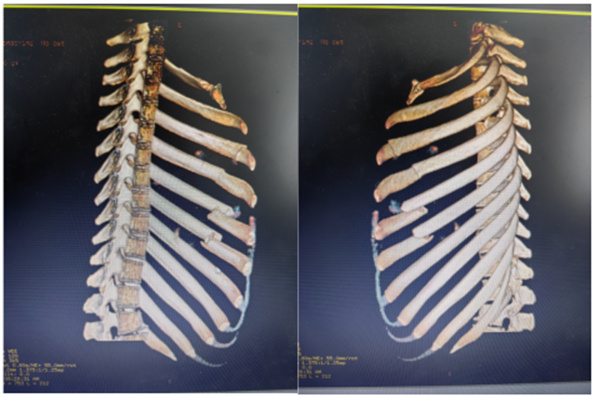

10:40,救护车飞驰而至,早已等候在急诊室门口的医务人员迅速将患者送到抢救室。接诊医师迅速诊治,发现患者王某肋骨多发骨折合并眼眶、多处损伤。急诊科立即成立创伤抢救小组,伤情就是命令,时间就是生命!急诊科医务人员闻令而动,迅速启动急救绿色通道!抢救护士立即建立静脉通路快速输液,止血、吸氧、监护、吸痰、验血、床旁超声检查......一系列急救措施在紧张而有序地进行着。经过快速CT检查,患者右侧眶周及颜面部软组织肿胀伴血肿形成、局部积气,右眼眶内侧壁骨折,右眼眶内积、内直肌损伤,左侧多发肋骨骨折,左侧血气胸。

正当患者王某前往内儿医技综合楼时,急促的电话铃声再次响起,电话那端传来120出诊护士的声音“又一位车祸伤患者正在送往我院,请马上做好抢救准备”!抢救小组的心再次悬了起来,11:30分救护车抵达医院,医务人员迅速将患者接至抢救室,经过检查,患者陈某胸骨体骨折,双侧多发助骨骨折,胸12椎体右侧附件骨折,腰1、2椎体右侧横突骨折,右侧气胸,双侧胸腔积液。

经抢救室快速处置和完善检查后,患者很快收治急诊EICU,收住院后急诊科副主任杨林东带领团队仔细评估患者伤情,制定了周密的手术计划,成功为王某完成左侧多发助骨骨折内固定术+胸腔镜探查术+膈肌破裂修补术,为陈某完成左侧多发助骨骨折内固定术+胸骨骨折固定术+胸腔镜探查术+肺破裂修补术,术后经过专业的医护团队精心护理,两位患者目前生命体征平稳,已转入普通病房继续治疗。